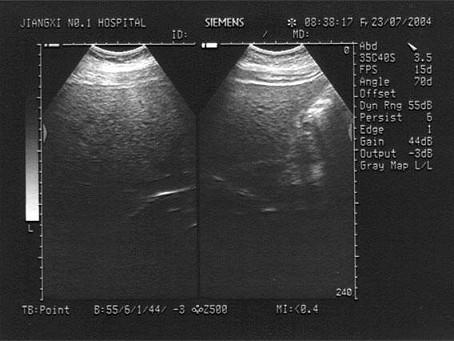

男,19岁。上腹部不适,肥胖。结合超声声像图,诊断为?(?)A.肝癌B.肝硬化C.脂肪肝D.肝炎E.肝豆状核变性

问题 男,19岁。上腹部不适,肥胖。结合超声声像图,诊断为?(?)

选项 A.肝癌 B.肝硬化 C.脂肪肝 D.肝炎 E.肝豆状核变性

答案 C